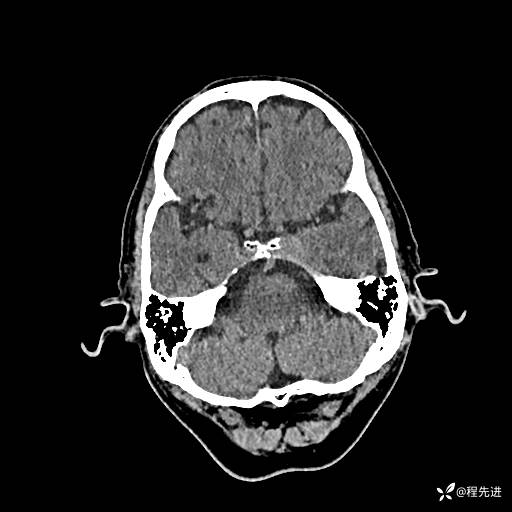

CT平扫: